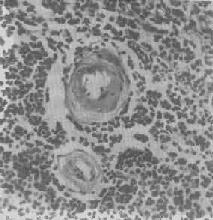

脾中央动脉玻璃样变

图1-20 脾中央动脉玻璃样变

中央动脉管壁明显增厚,呈玻璃样均质状,管腔变窄